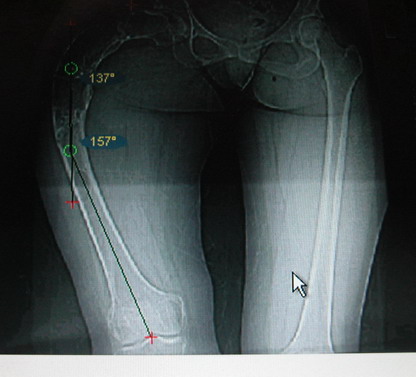

На мой взгляд, для того, чтобы правильно исправить данную деформацию, необходимо обследование больного, которое должно включить в себя, помимо осмотра: 1. Рентгенограммы ( передне-задние и боковые)нижних конечностей на всю длину стоя . 2. Компьютерная томография для измерения длины нижних конечностей. 3. Комьютерная томография тазобедоенных, коленных и голеностопных суставов для измерения углов антеверсии тазобедренных суставов и ротации голеней. Это тот минимум, который должен входить в предоперационное обследование каждого больного с тяжёлыми формами деформаций конечностей.

Поскольку в данном случае имеется дело с довольно большой деформацией с укорочением, одномоментная её устранение с внутренней фиксацией, чревато с одной стороны неправильной коррекцией, с другой, нейроваскулярными осложнениями.

Моё мнение, что двойная остеотомия бедра с аппаратом Илизарова + Гексаподный механизм, или Тэйлора, В данной ситуации является методом выбора. Я очень извеняюсь за качество прилагаемых снимков, в которых я постарался отразить разницу междe одной и двумя остеотомиями бедра.